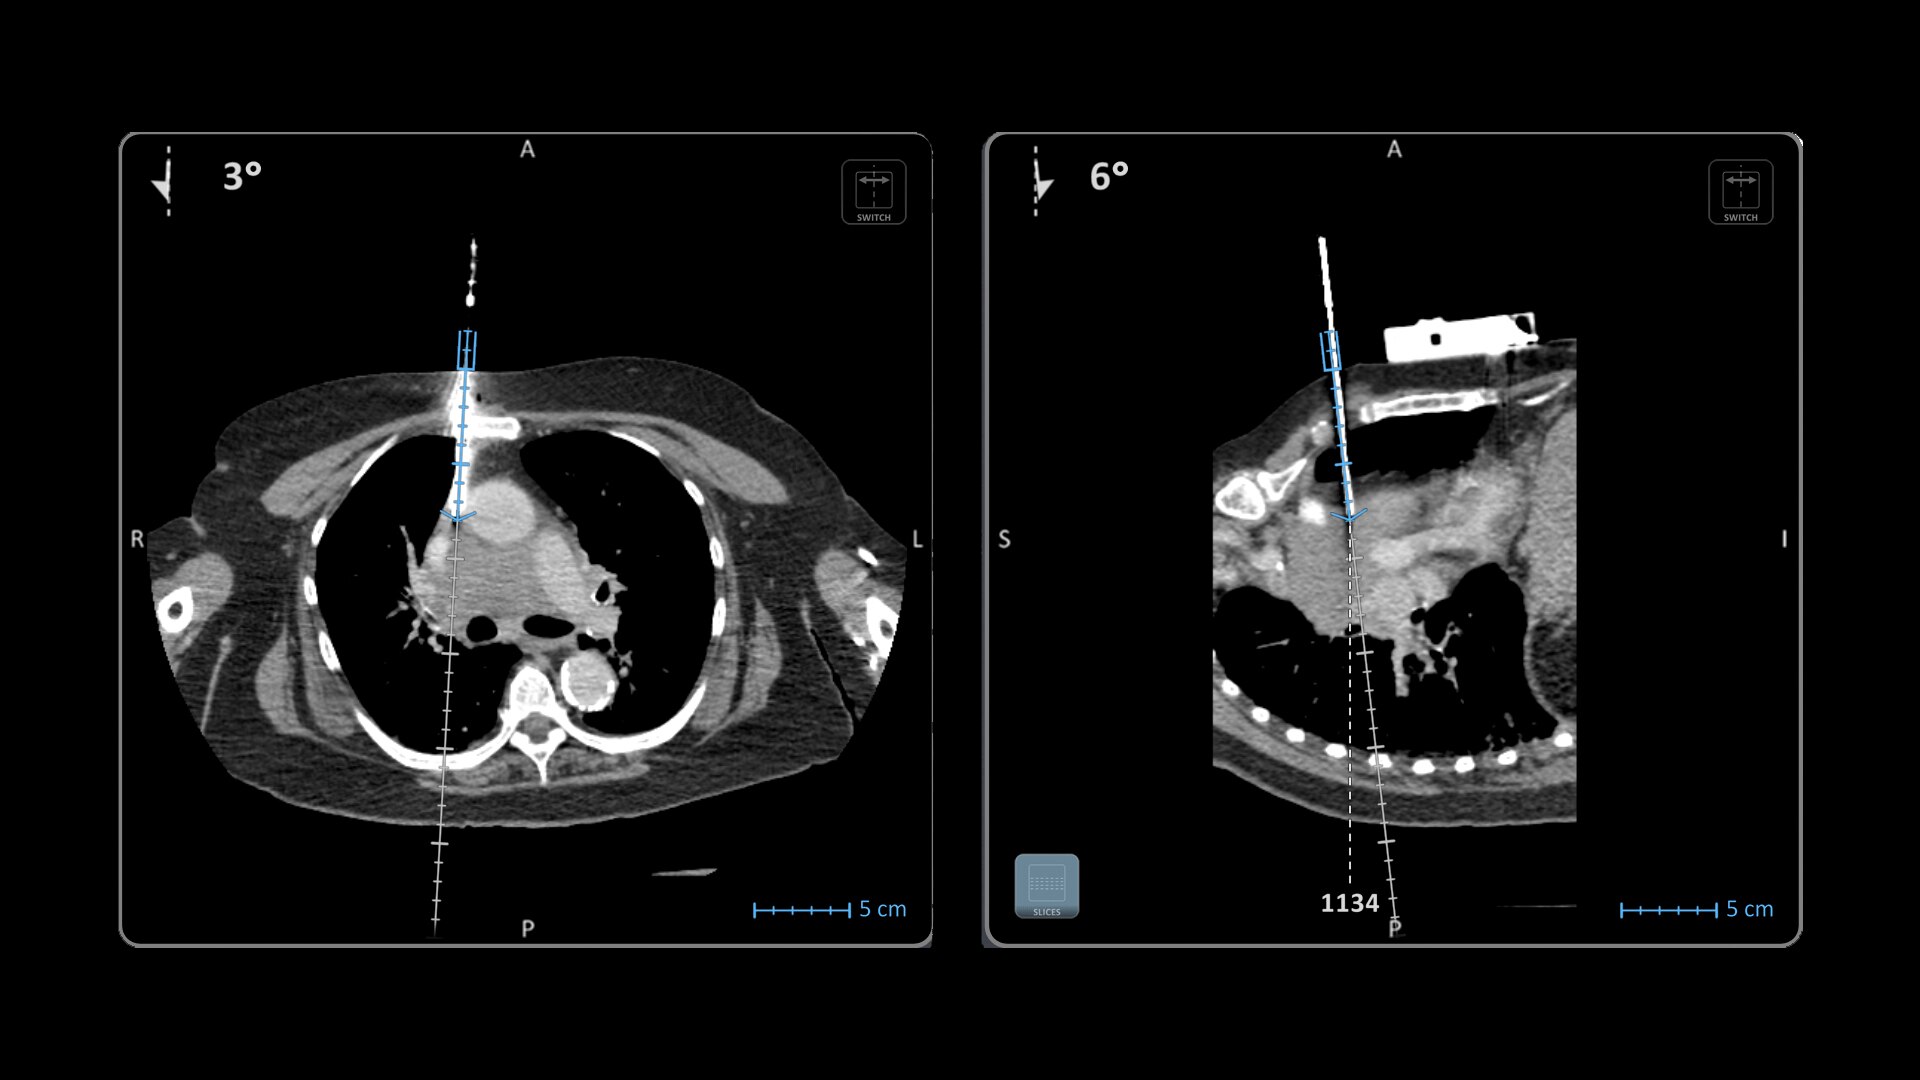

Imactis® CT-Navigation™

Planning and navigation solution for interventional percutaneous radiology.

Improve accuracy to reach target and avoid critical structures and organs¹

Imactis® CT-Navigation™ is an electromagnetic (EM) navigation solution for CT-guided percutaneous procedures

Imactis® CT-Navigation™ is designed to radically improve efficiency of Interventional procedures for clinicians and hospitals by increasing their accuracy.